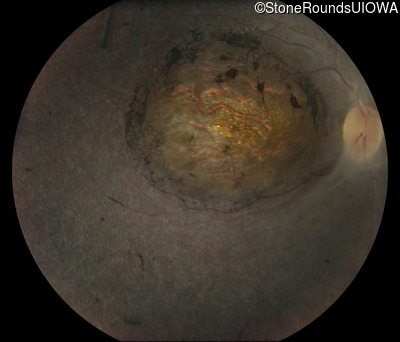

Fundus Photography - Right - Light Perception

Exemplar